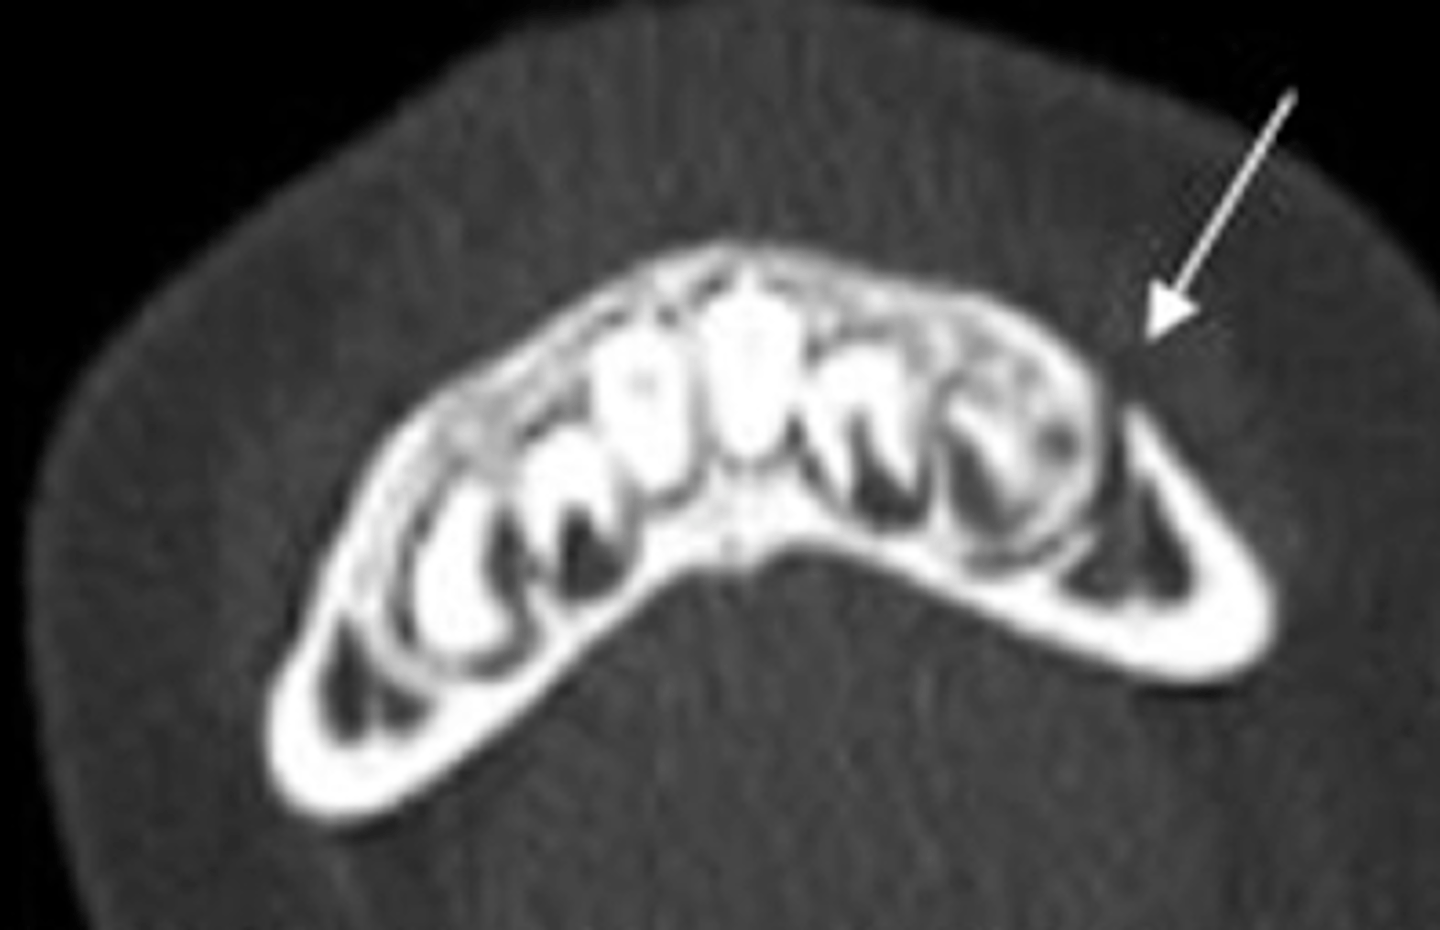

Greenstick

A 4 year old female patient fell off her scooter and struck her face. She was wearing a helmet and had no loss of consciousness but reported pain in her left lower jaw. She went to her local Children's Hospital where a CT was taken showing this injury. What type of fracture is this?

- Simple

- Comminuted

- Greenstick

- Complex